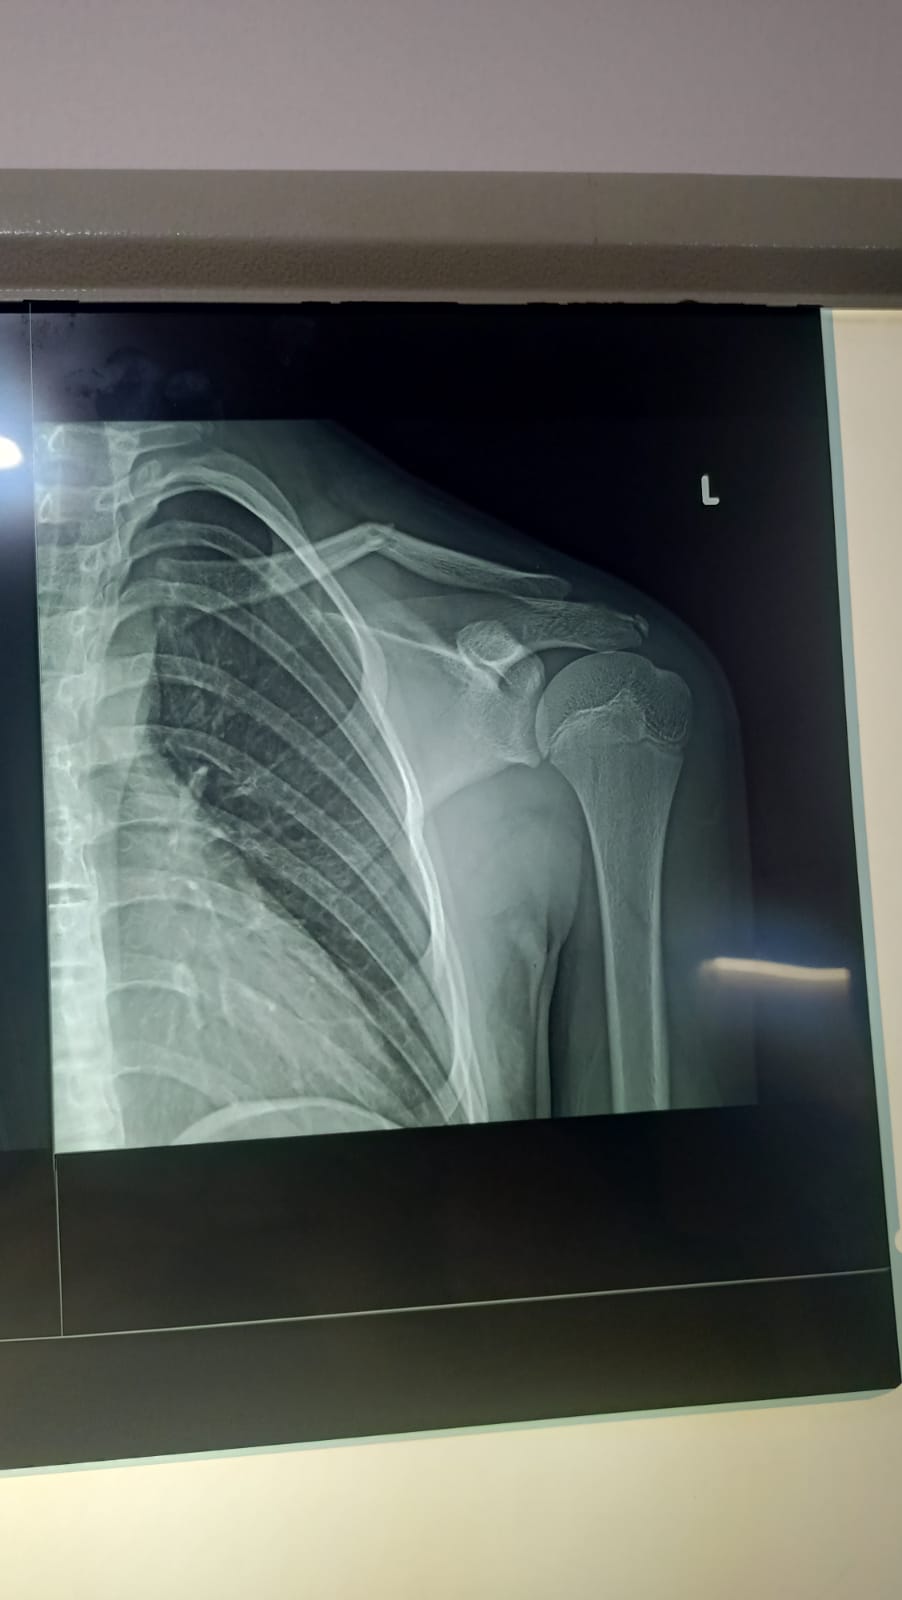

16 yr boy had bike accident 4 days ago,this is his x ray .he is having sling.. now he is feeling sweling on the guide..

his clevicle ( also known as beauty bone ) is fractured . kindly consult some orthopedic for further management .

green stick /undisplaced collar bone(clevicle) ,nothing to worry much,

needs to see pt for other injury,

this fracture will heal on it own,

nothing to do special except to apply a sling/collar and cuff bandage if available to avoid further deformity or displacement....

painkillers like paracetamol and calcium supplements should b given make him pain free and achieve good healing of the bone

If there is skin tenting then it should be operated.042-32591427, kindly contact for further evaluation

Keep in sling for four weeks. Seedling will be reduced with time 2-3 weeks.

He only needs sling for comfort. Bone will heal well. Swelling will go in 6 months. No need for operation- start moving shoulder next week

press clavicle down for reductions and cp bandage 8 of figer plus poly sling for 3 to 4 weeks after that cheek x rays plus start physiotherapy no surgery required